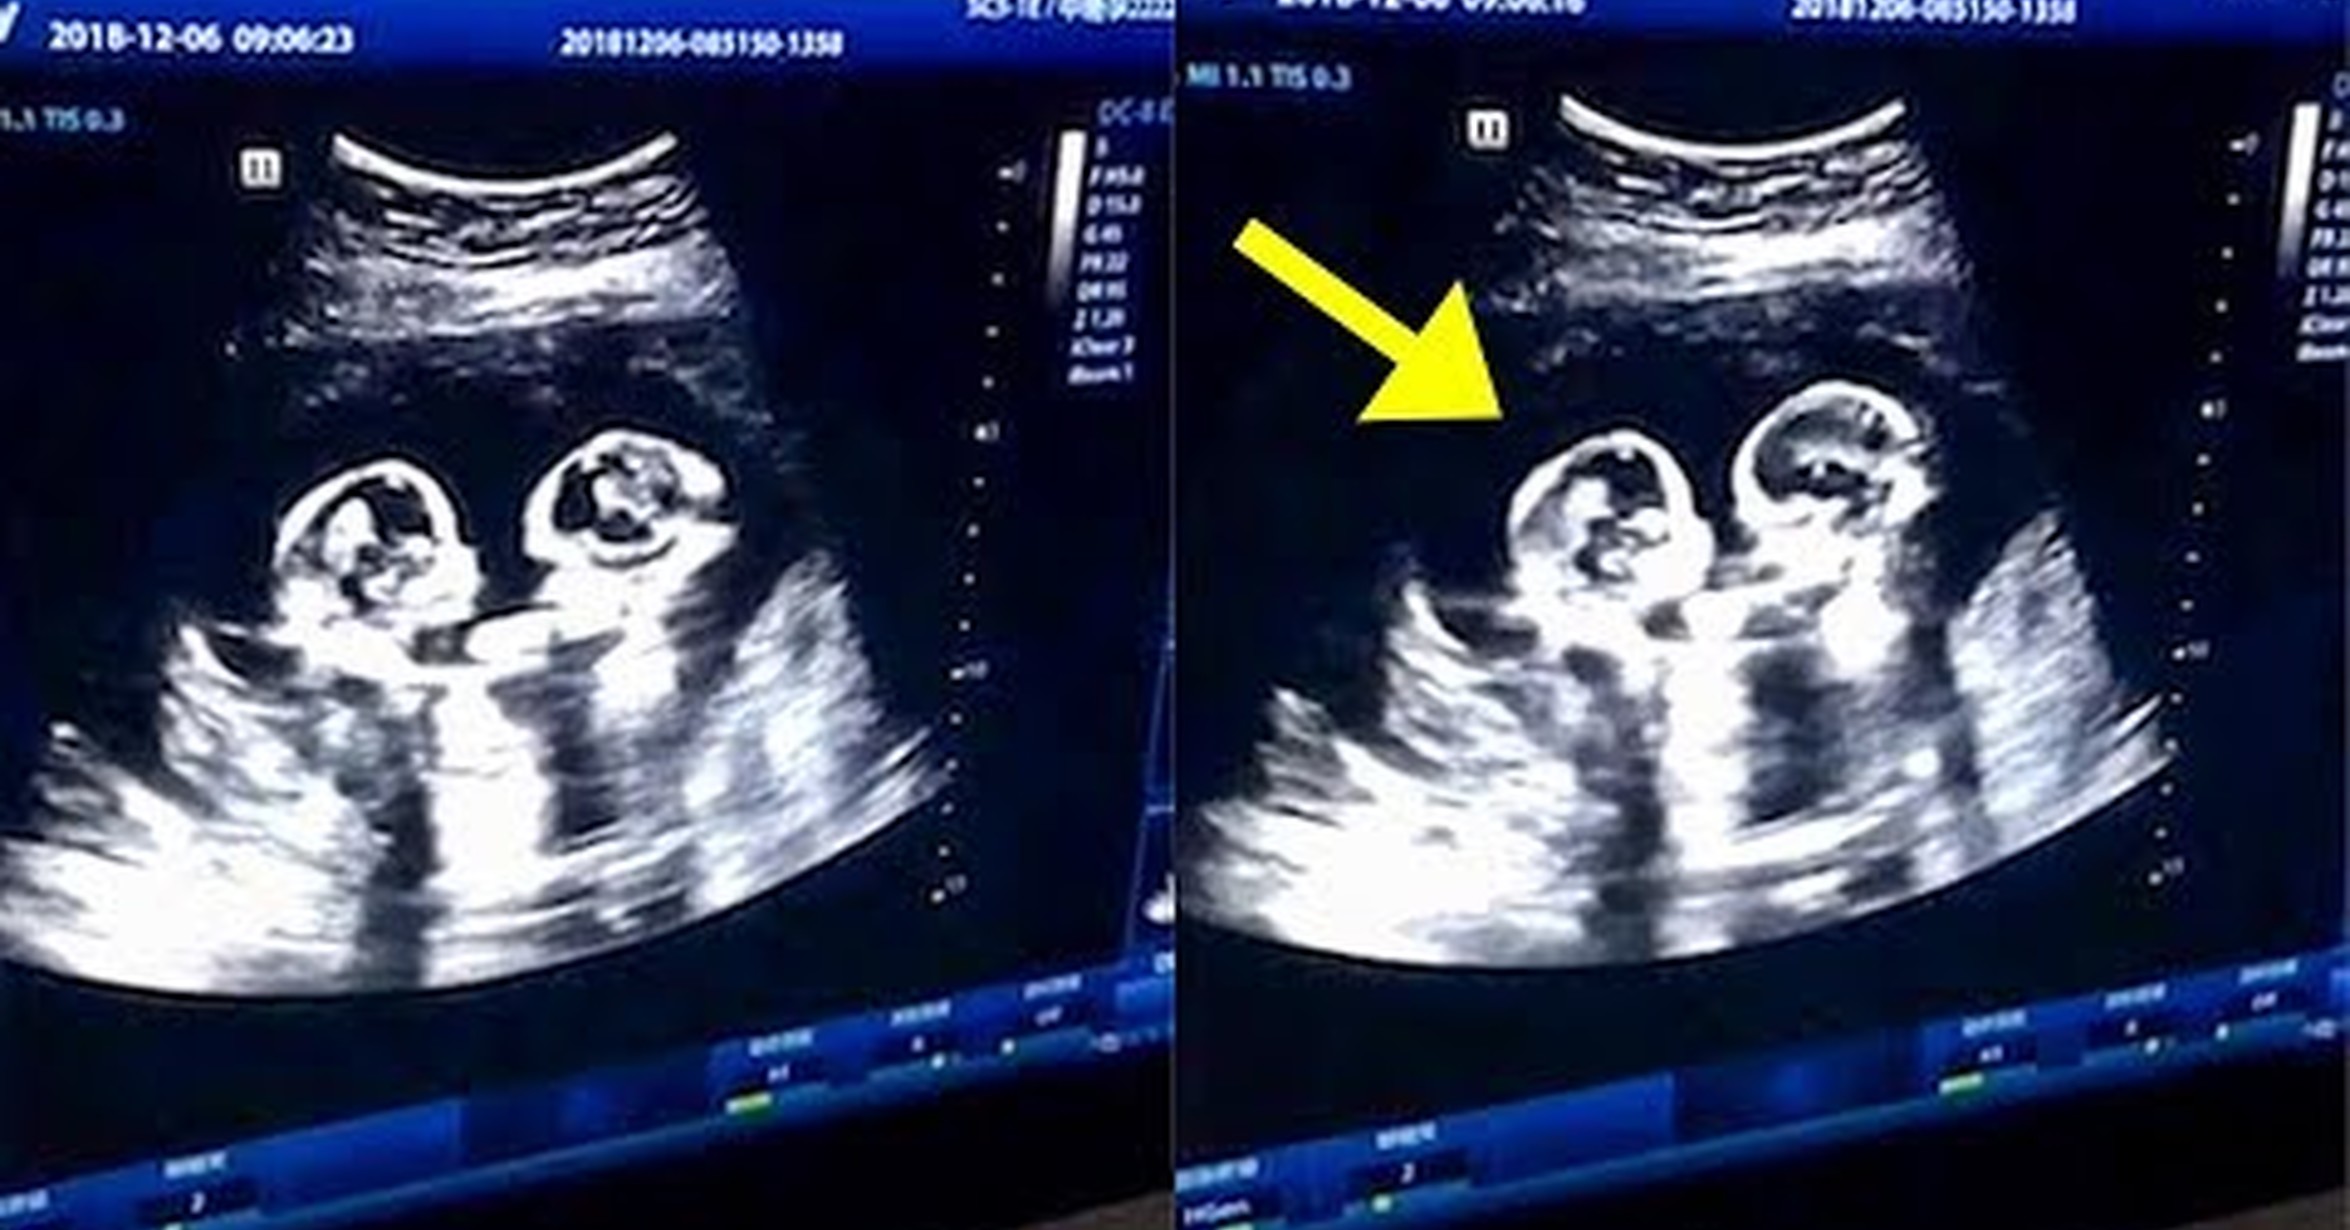

Фото Двойняшек В Утробе Матери 108 фото